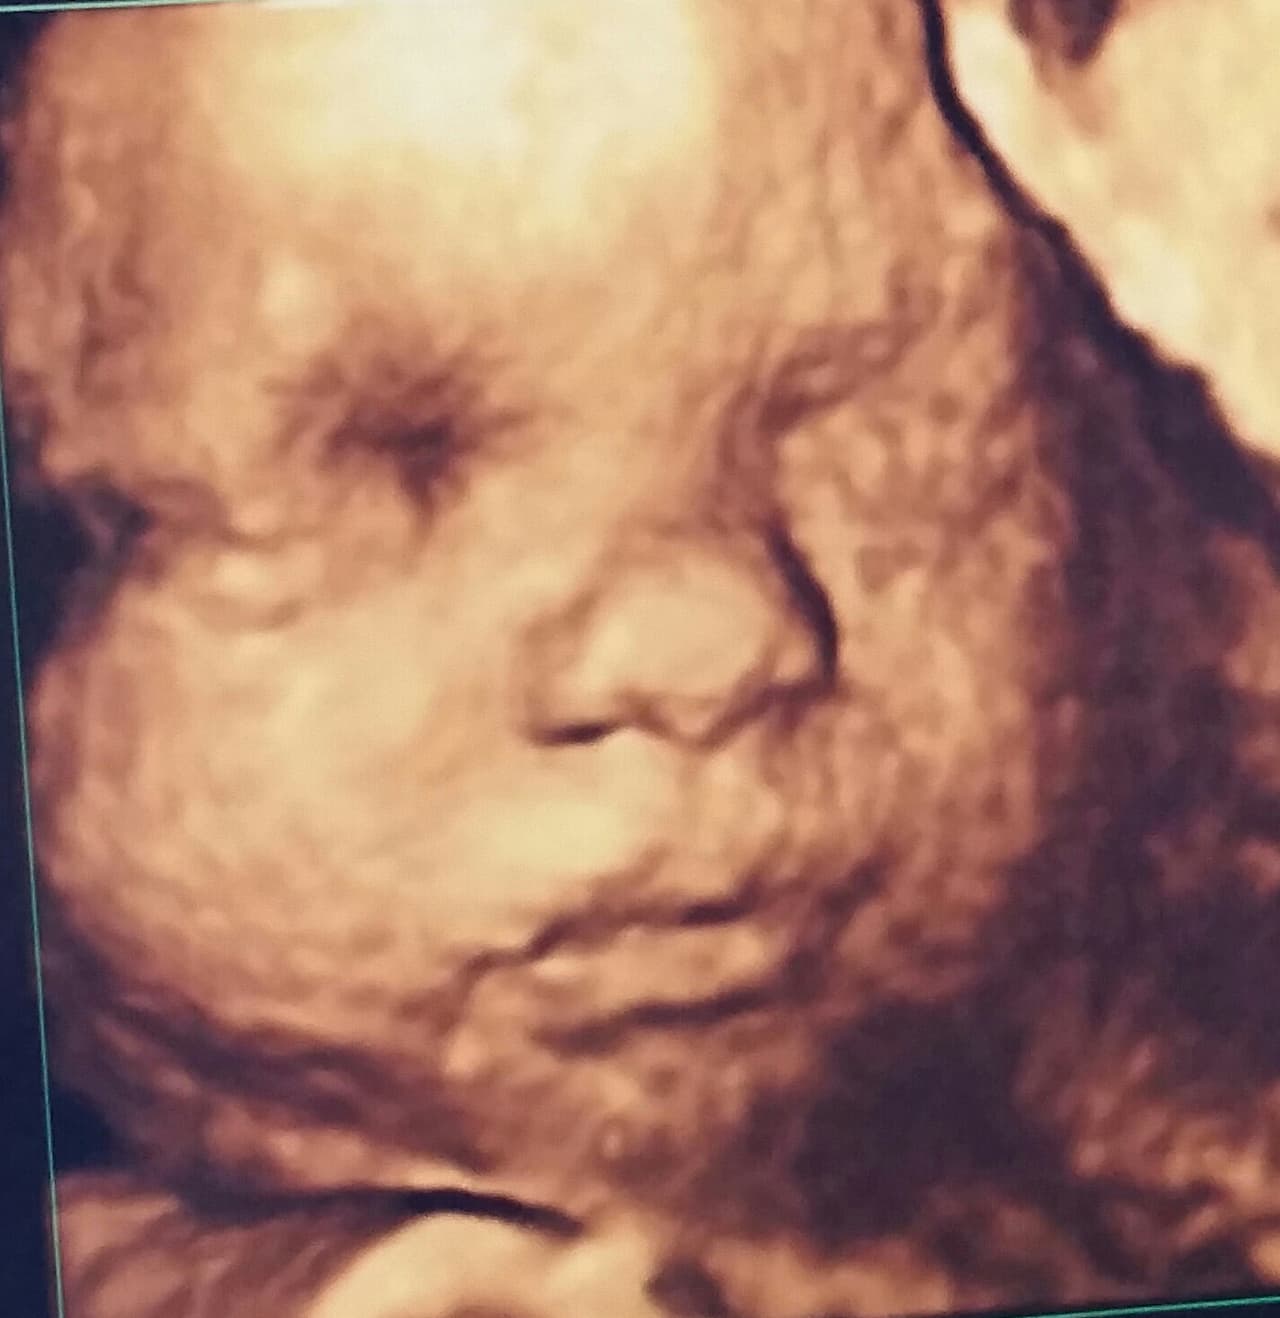

La presentadora se goza su maternidad al máximo y nos compartió su sonograma 4D.

Gredmarie, quien a sus 15 semanas de gestación, dio a conocer el sexo de su bebé durante la transmisión en vivo de Rubén & Co, vive encantada de tener una niña y por eso compartió con sus seguidores en Rubén & Co. la experiencia de ver a su bebé en un sonograma 4D.